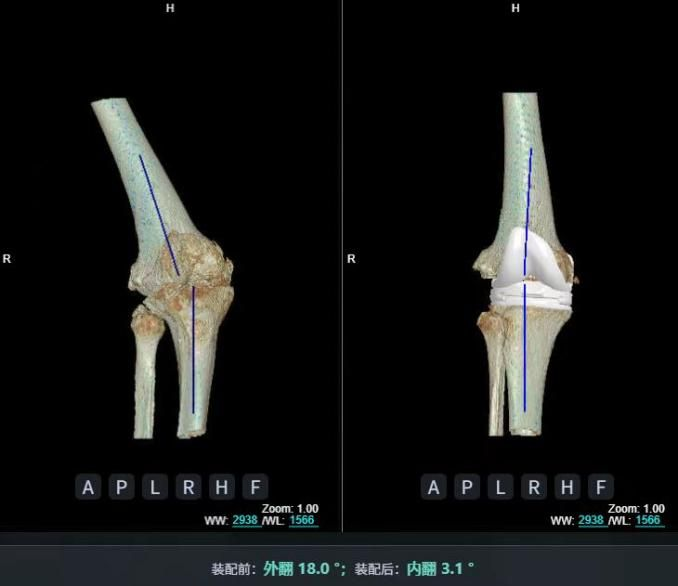

4.2 APTT-HTO脛骨高位截骨術(shù)

2025年7月,貴州醫(yī)科大學(xué)附屬醫(yī)院骨科團(tuán)隊(duì)原創(chuàng)研發(fā)的腘肌前結(jié)節(jié)中脛骨高位截骨保膝術(shù)(Anterior Popliteus Transtibial Tuberosity-High Tibial Osteotomy, APTT-HTO)及其提出的脛骨結(jié)節(jié)分區(qū)與腘肌保護(hù)理論,登上了國際頂尖學(xué)術(shù)舞臺。該成果在全球最具影響力的專業(yè)會議之一——日本骨科協(xié)會第98屆年會上進(jìn)行了兩次學(xué)術(shù)發(fā)言。[8]

該手術(shù)具有經(jīng)皮微創(chuàng)、保留原生膝關(guān)節(jié)結(jié)構(gòu)、符合階梯治療原則等優(yōu)勢,通過調(diào)整下肢力線可促進(jìn)部分軟骨再生,術(shù)后關(guān)節(jié)功能接近正常(如下蹲、爬山),患者還能從事中重體力勞動。相比其他術(shù)式,其有效規(guī)避了髕骨低位、血管損傷、合頁骨折等潛在并發(fā)癥。

目前,APTT-HTO技術(shù)已成功應(yīng)用于千余名患者,幫助保留自身膝關(guān)節(jié)。此類保膝手術(shù)適用于單間室膝關(guān)節(jié)炎患者(如 “羅圈腿”),核心是通過調(diào)整力線糾正畸形,減輕磨損間室壓力、發(fā)揮健康間室作用,延長膝關(guān)節(jié)壽命。若出現(xiàn)膝關(guān)節(jié)疼痛、保守治療無效且X線顯示關(guān)節(jié)間隙部分狹窄,建議及時就醫(yī)評估是否適合手術(shù)。

APTT-HTO脛骨高位截骨術(shù)